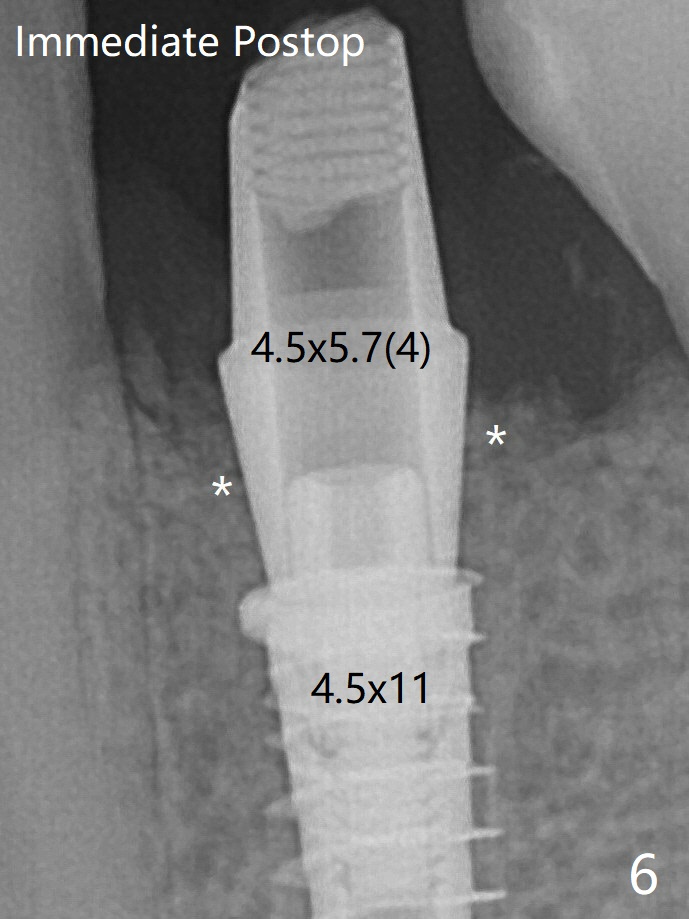

术后4个月骨粉好像不能形成牙槽嵴(图十二,与图五,六对比)。牙冠间隙可能无关大局(<)。